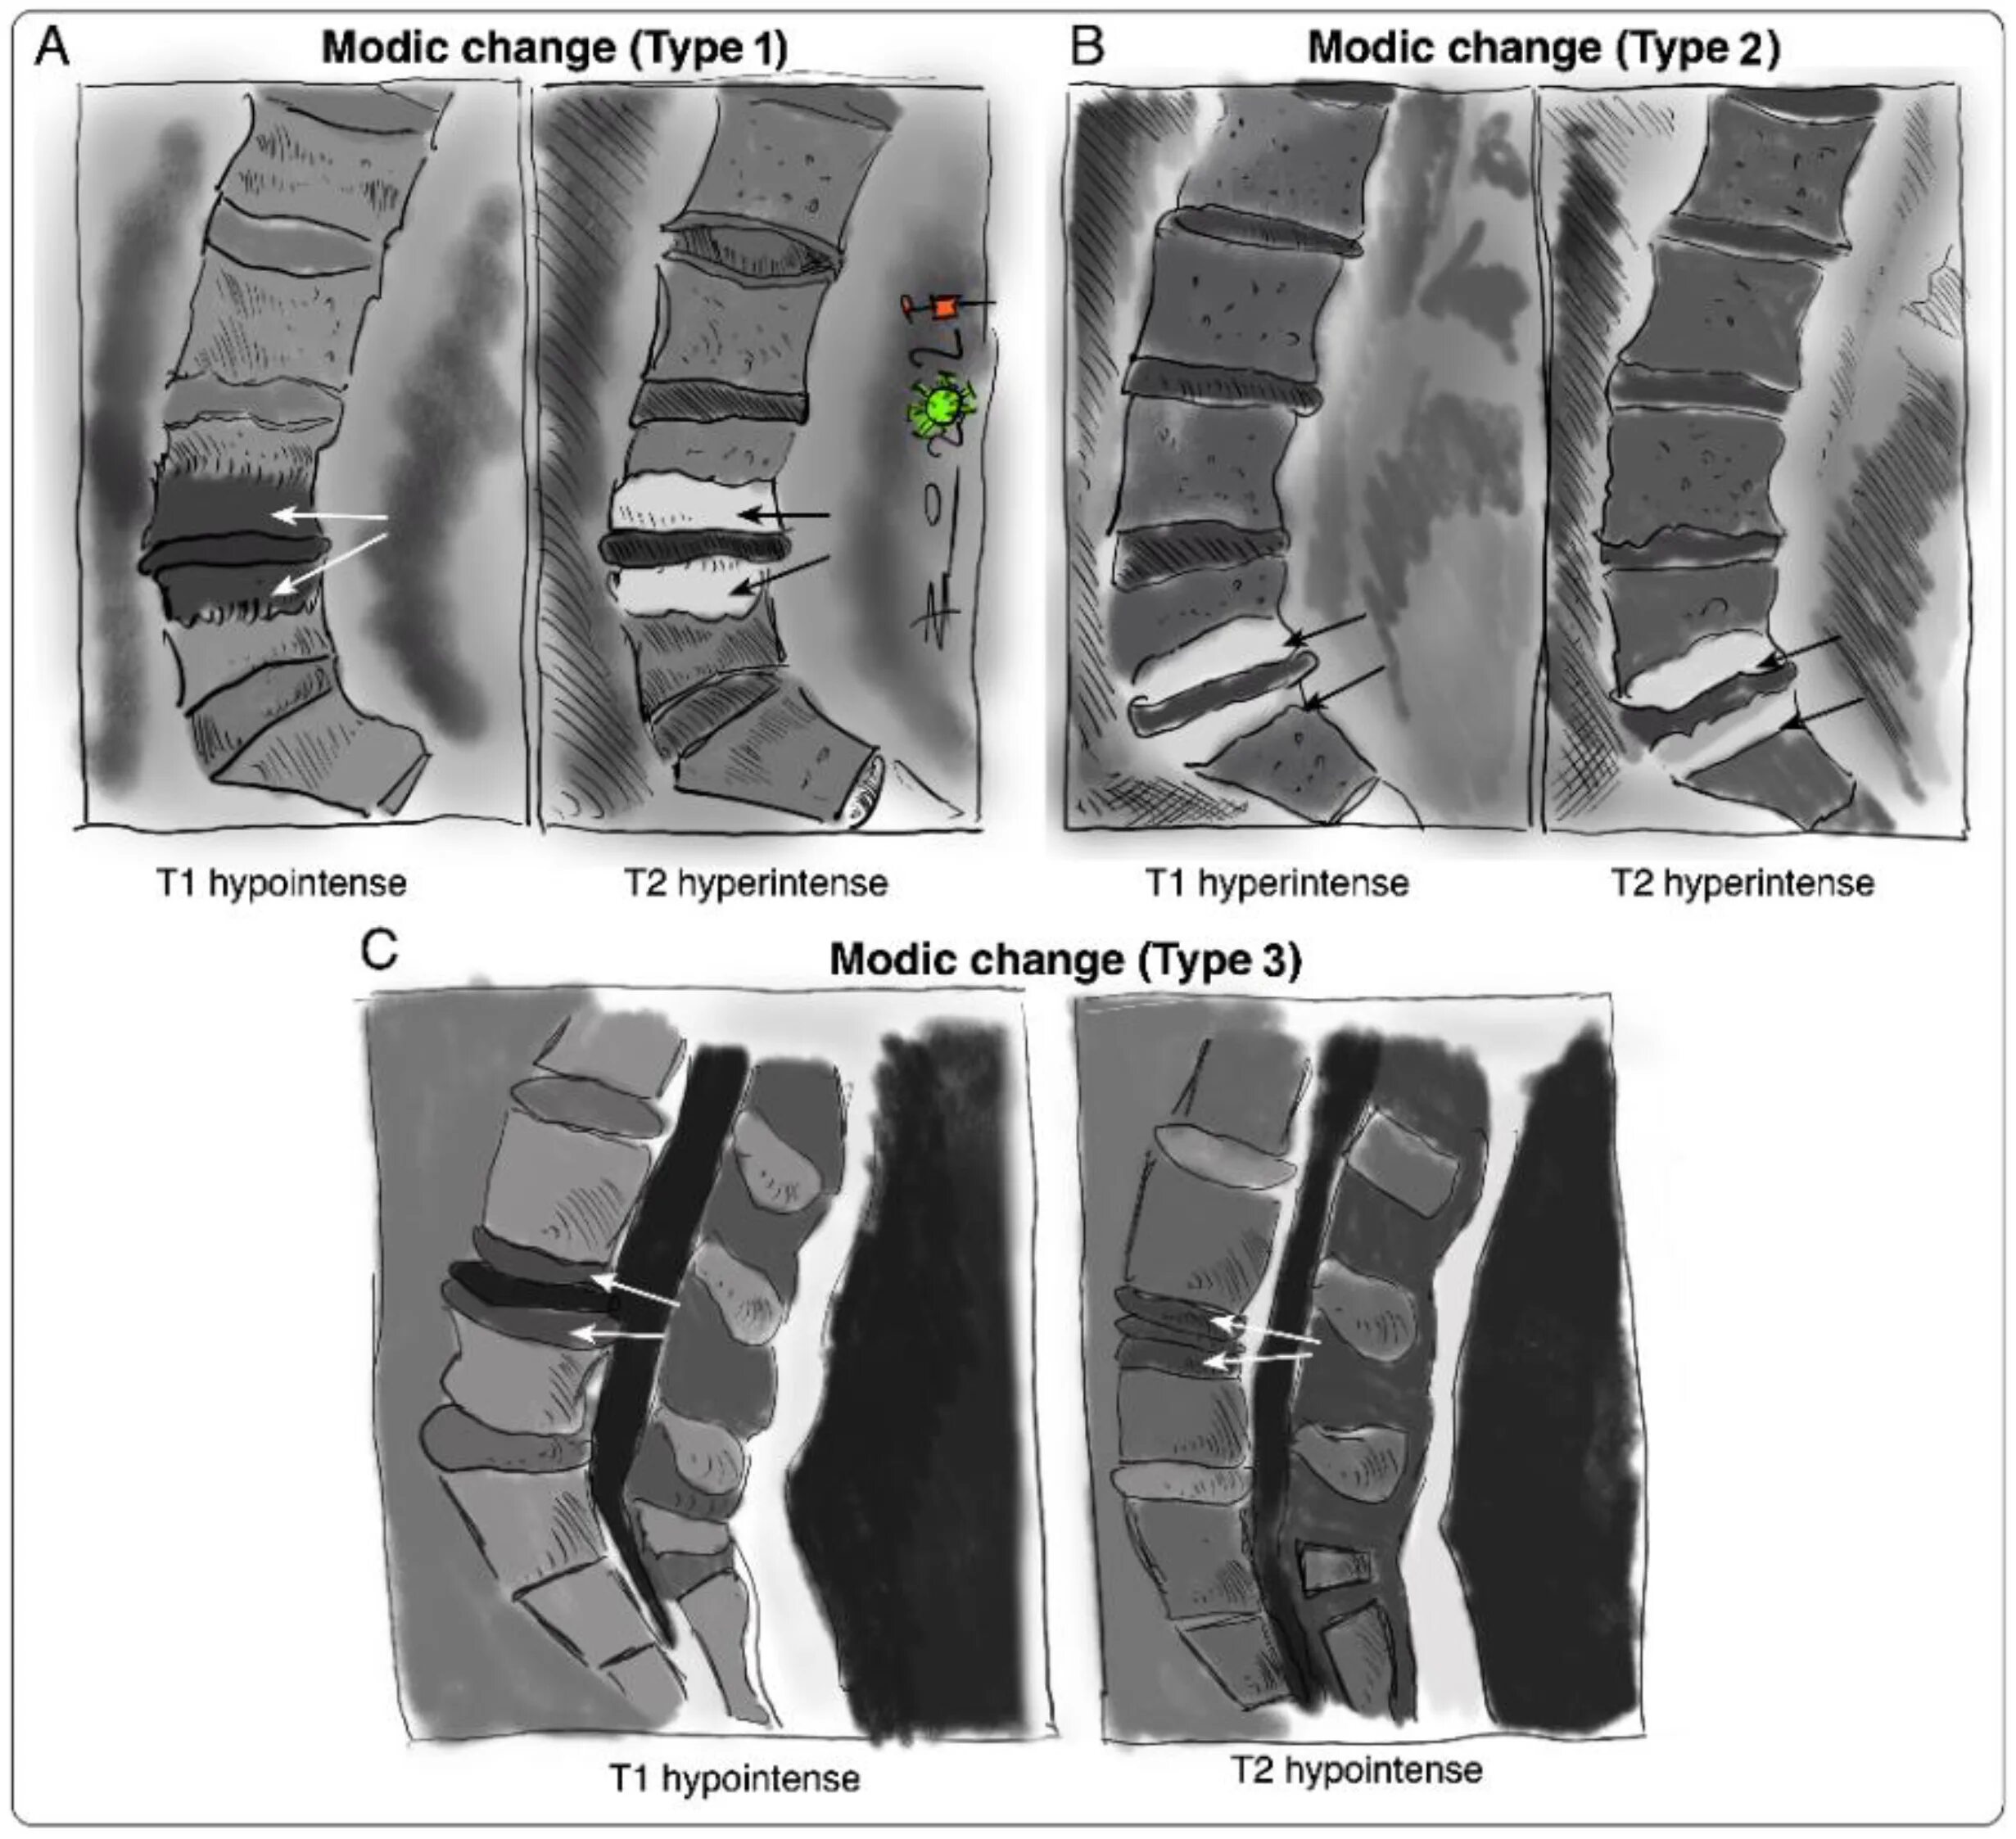

Изменения modic 2